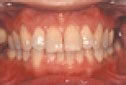

♦健康な歯肉

歯肉の色:薄いピンク色。

歯肉の形態:歯と歯の間に入り込んで弾力があり、引き                    締まっている。

ブラッシングでは出血しない。